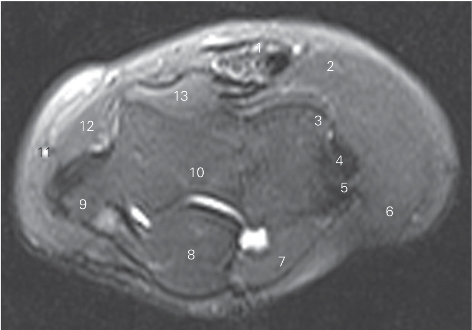

图4-32 经肘关节上份的横断层MR T2WI FS

1 肱二头肌腱 tendon of biceps brachii 2 肱桡肌 brachioradialis

3 肱骨小头 capitulum of humerus

4 桡侧副韧带 radial collateral ligament

5 肱骨外上髁 lateral epicondyle

6 桡侧腕长、短伸肌 extensor carpi radialis longus and brevis

7 肘肌 anconeus 8 尺骨鹰嘴 ulnar olecranon

9 肱骨内上髁 medial epicondyle of humerus

10 肱骨滑车 trochlea of humerus 11 贵要静脉 basilic vein

12 旋前圆肌 pronator teres 13 肱肌 brachialis